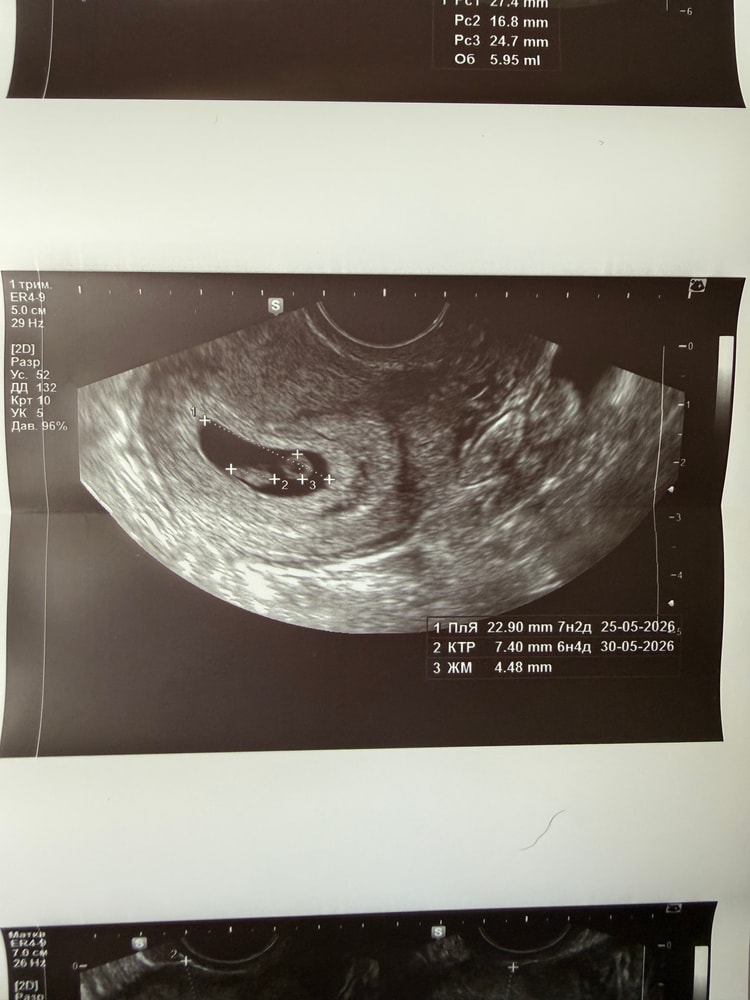

По М срок 7.4

По КТР - 6.4

По ПЯ - 7.2.